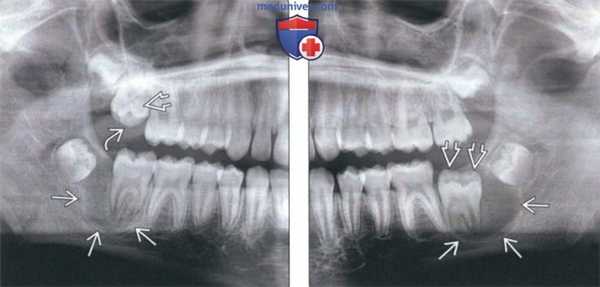

(Слева) На кадрированной панорамной рентгенограмме определяется хорошо отграниченное просветление, связанное с корнем второго постоянного моляра нижней челюсти справа у мальчика 11 лет. Обратите внимание, что жевательная поверхность непрорезавшегося второго постоянного моляра в верхней челюсти справа расположена под углом, а язычные бугорки находятся в возвышенном положении.

(Справа) На кадрированной панорамной рентгенограмме у этого же пациента определяется похожее просветление, хорошо отграниченное кортикальной пластинкой, связанное с вторым моляром нижней челюсти слева. Обратите внимание на выбухание язычных бугорков.